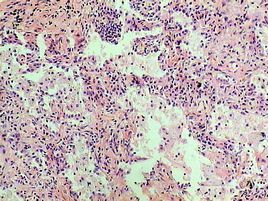

肺孢子蟲屬低致病力、生長繁殖緩慢的寄生性原蟲,健康宿主有抵禦能力只形成隱性感染。細胞免疫受損是宿主最主要的易患因素,如嬰幼兒營養不良,先天性免疫缺陷兒童,惡性腫瘤、器官移植或接受免疫抑制治療及AIDS患者。在AIDS病人中的發病高達80%~90%。當T細胞免疫功能抑制時,寄生於肺泡的肺孢子蟲可大量繁殖,對上皮細胞造成直接的毒素性損害,引起I型上皮脫屑性肺泡炎。肺泡間隔有漿細胞,單核細胞浸潤,肺泡上皮增生,增厚,泡腔內充滿嗜酸性泡沫樣物質和蛋白樣滲出物。嚴重病例有廣泛間質和肺泡性水腫。肺泡腔內充滿炎性細胞,蛋白樣滲出物和蟲體,阻礙氣體交換,產生臨床症狀。

3.病原學檢查痰、支氣管肺泡灌洗液,經纖支鏡肺活檢做特異性的染色如吉姆薩(Giemsa)染色、亞甲胺藍(TBO)染色、Gomori大亞甲基四胺銀(GMS)染色,查獲含8個囊內小體的包蟲為確診依據。